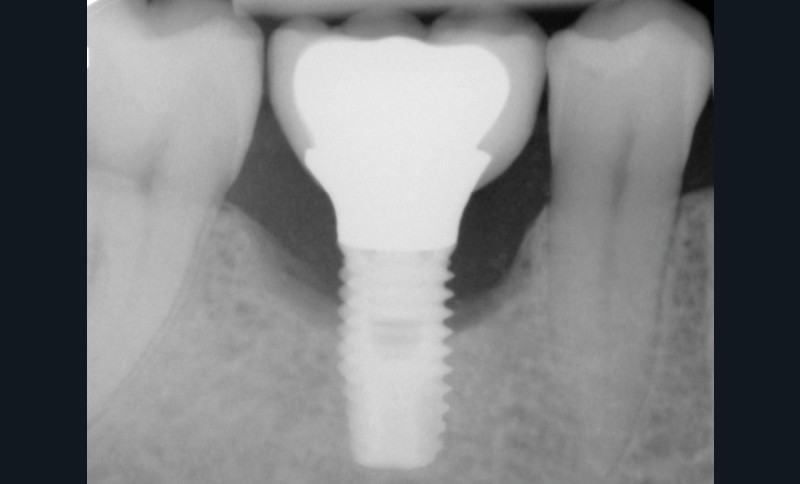

Les critères qui permettent de diagnostiquer une péri-implantite sont aujourd’hui bien établis, les voici rappelés : signes cliniques d’une inflammation péri-implantaire (gonflement, rougeur, saignement au sondage et/ou suppuration) (fig. 1a), perte osseuse péri-implantaire au-delà de celle constatée après la cicatrisation « initiale » (fig. 1b), augmentation de la profondeur de poche au sondage en comparaison de la profondeur de poche identifiée lors de la mise en place de la restauration prothétique [2, 23]. En l’absence de documents radiographiques préexistants, une perte osseuse supérieure ou égale à 3 mm en association avec un saignement au sondage et une profondeur de poche au sondage supérieure ou égale à 6 mm permet également de poser le diagnostic de péri-implantite [23].